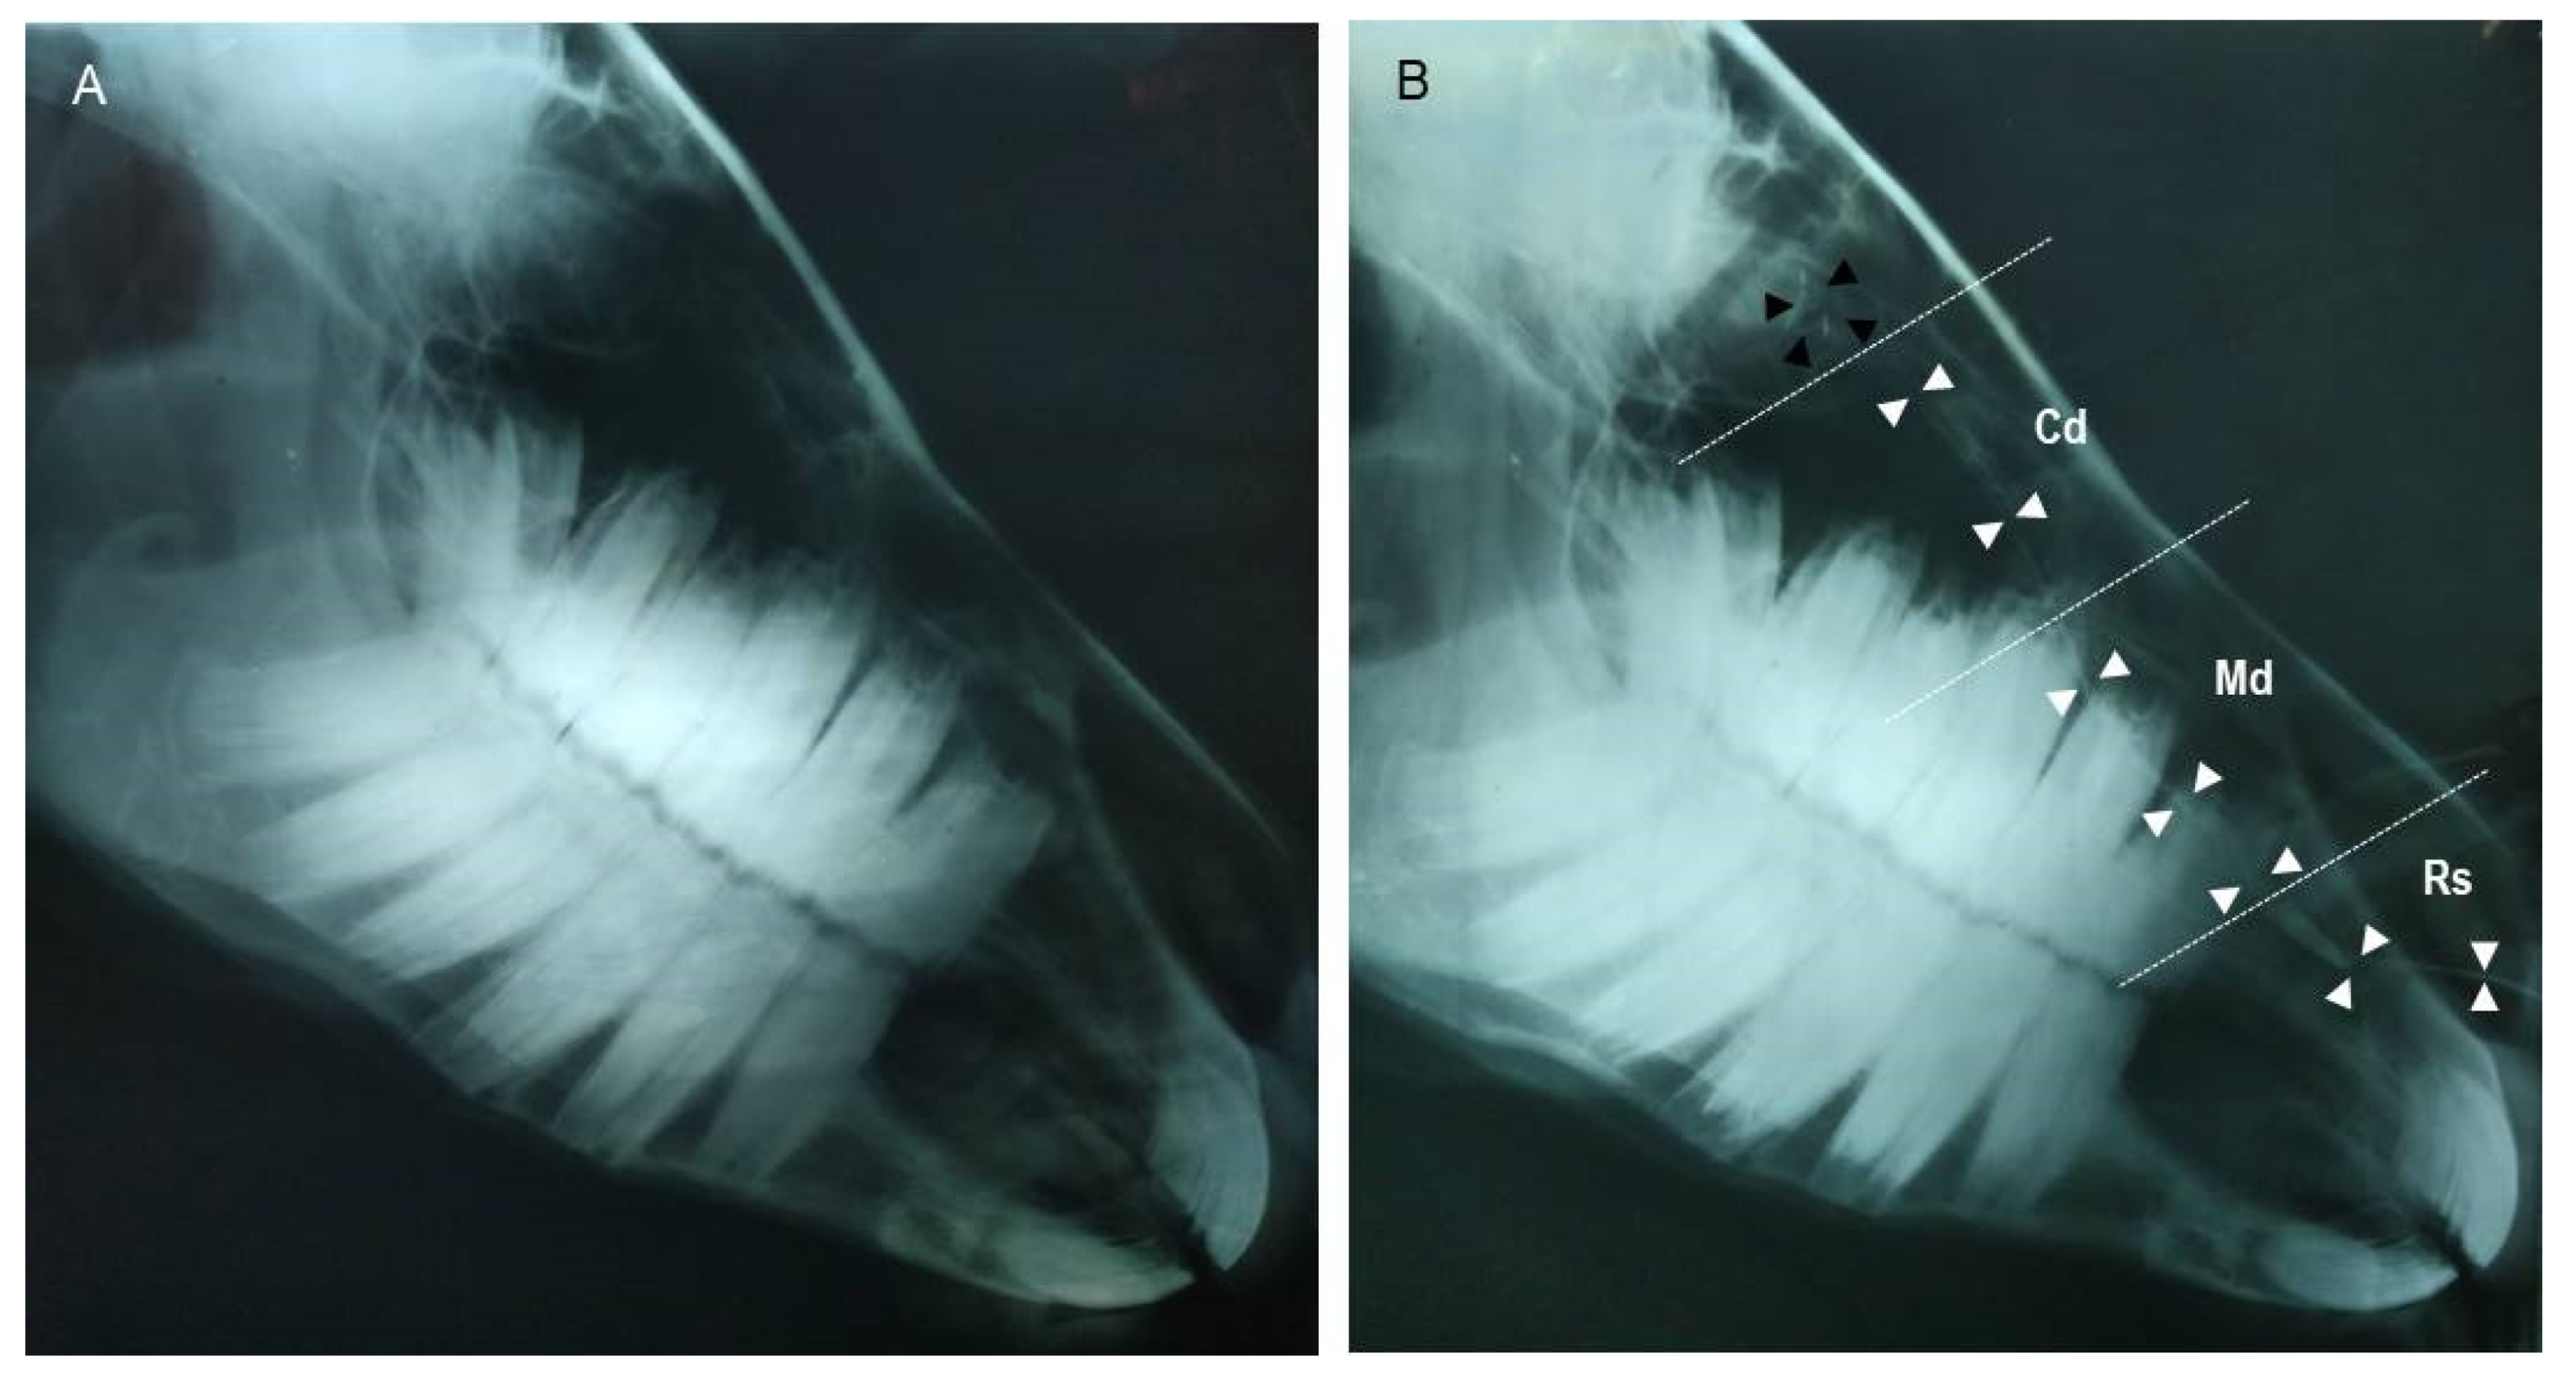

3.2. Dacryocystorhinography

| Radiography | Nasolacrimal duct rostral (NLDRs) diameter | 4.1 | 4.9 | 4.5 (0.2) |

| Nasolacrimal duct middle (NLDMd) diameter | 2.2 | 2.9 | 2.6 (0.2) | |

| Nasolacrimal duct caudal (NLDCd) diameter | 0.8 | 1.5 | 1.1 (0.2) | |

| Nasolacrimal duct (NLD) length | 172.0 | 209.0 | 193.0 (9.8) | |

| Nasolacrimal duct (NLD) rostral cartilaginous | 60.0 | 79.0 | 67.4 (4.9) | |

| Nasolacrimal duct (NLD) middle membranous | 60.0 | 81.5 | 67.9 (6.0) | |

| Nasolacrimal duct (NLD) caudal osseous | 60.0 | 79.0 | 67.2 (5.1) | |